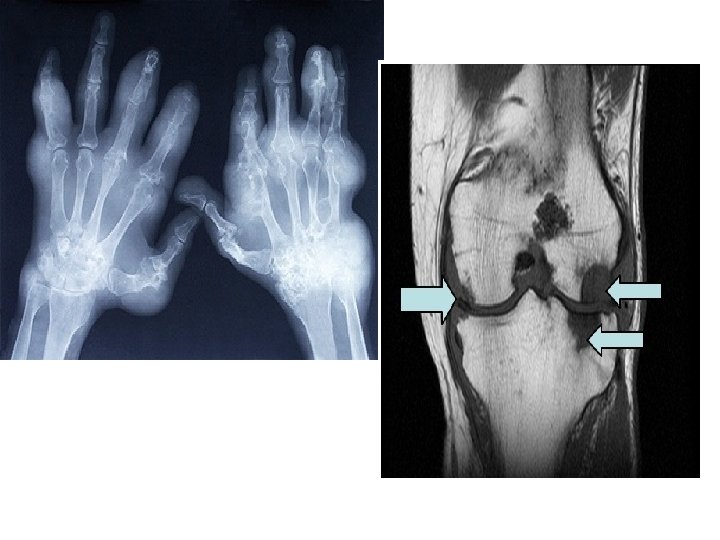

Arthritis

Gout • Gout is a disease that results from an overload of uric acid in the body. • This overload of uric acid leads to the formation of tiny crystals of urate that deposit in tissues of the body, especially the joints. • When crystals form in the joints it causes recurring attacks of joint inflammation (arthritis). • Chronic gout can also lead to deposits of hard lumps of uric acid in and around the joints and may cause joint destruction, decreased kidney function, and kidney stones.